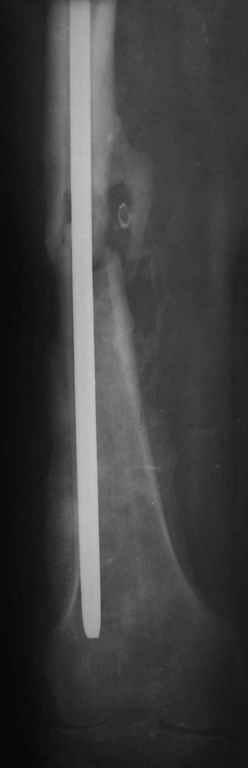

Рутинный интрамедуллярный остеосинтез с расверливанием и с фиксацией реконструктивным трокантерик штифтом (рис №1, №2),

если первые 4 месяца послеоперационного периода проходил без проблем, но на 5 месяце появились боли в дистальном отделе бедра и температура, т.е. симптомы медуллярного инфицирования (рис №3, №4).

Замена реконструктивного штифта “Custom made Nail” с антибиотиком (рис №5, №6),

после промывки канала с рассверливанием внутреннего кортекса, через 4 недели антибиотический штифт удалили, оспалителный процесс остановлен и бедро сросся.

При обзоре причин перелома, на снимке №2 обнаружили, что один из стержней аппарата наружной фиксации проходил только через передний кортекальный слой, что создало стрессовую зону на бедре и в результате перелом из-за незначительной травмы.